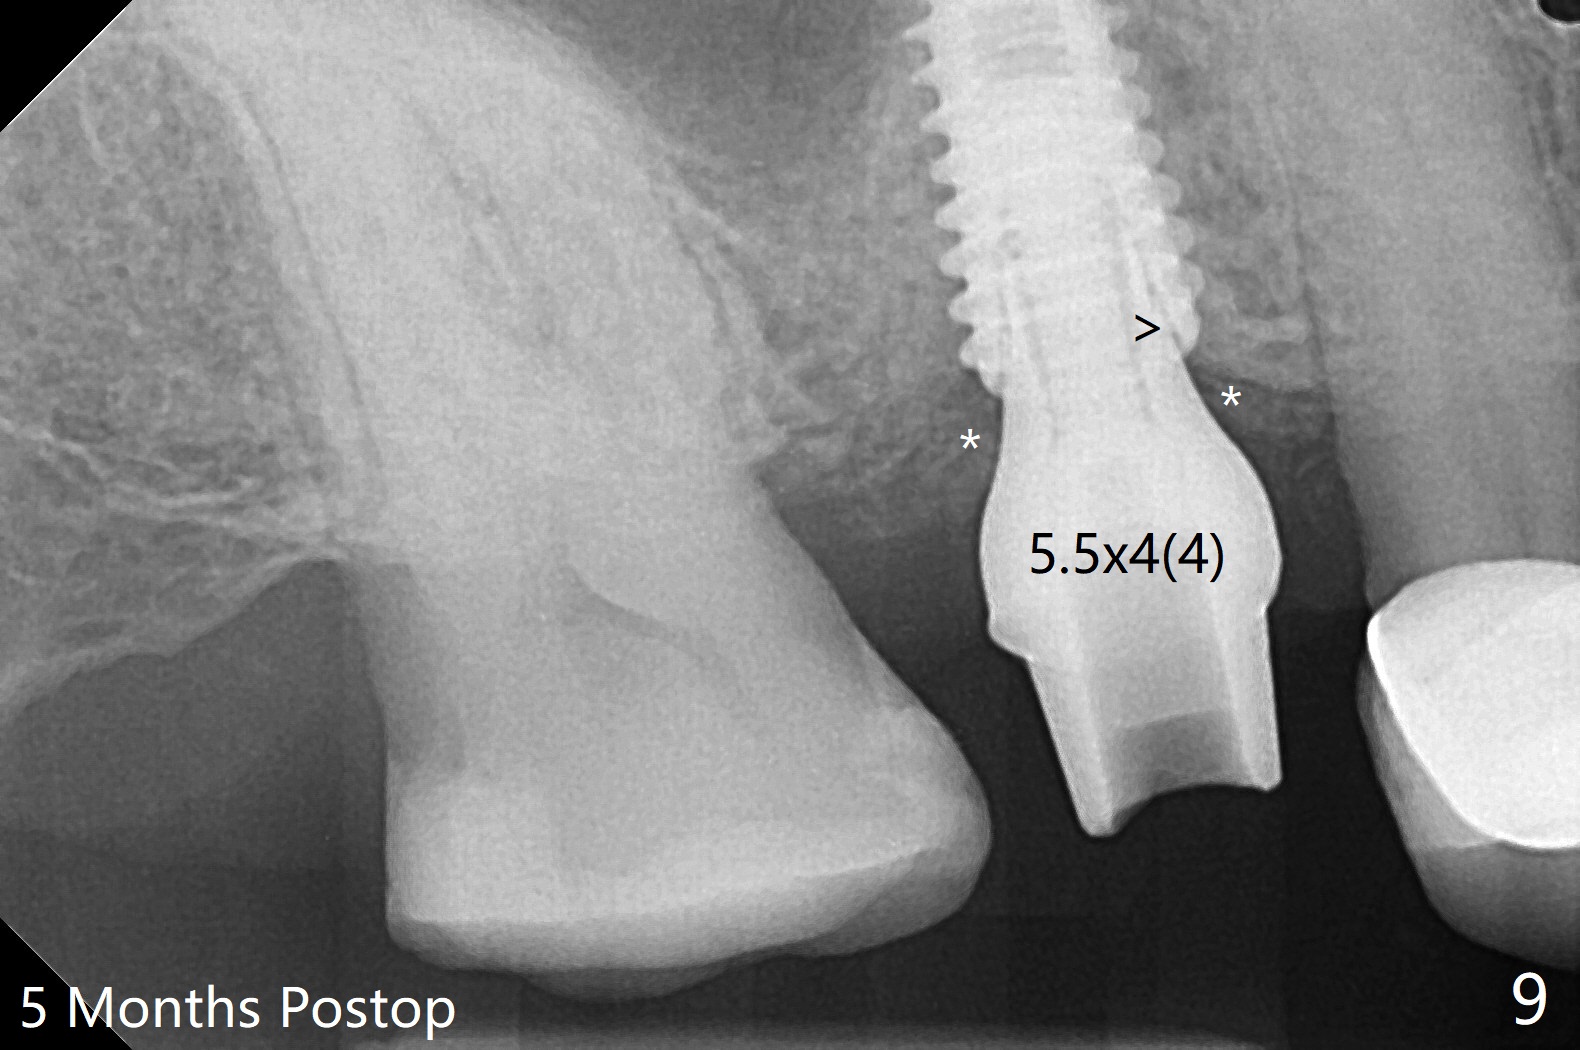

提取上清液后,红管再次离心,同样速度,5分钟,便形成PRF(胶状,上面黄色部分,图七),由于试管在离心机放置角度缘故,PRF与下面红血球部分(深色)交界处是一个斜面,制作PRF膜前,必须在交界处下面剪(图八白斜线),因为在交界处有效成分浓度最高,请看录像(虽然剪的太高些)。制作完毕的PRF膜可以覆盖图四骨块表面,但是用于图一之后,塞入上颌窦(录像),目的促进上颌窦膜修复,万一提升时出现隐形破裂。术后五个月放置5.5x4(4)毫米基台,未完全就位:基台与植体之间有间隙(图九:>),可能牙槽嵴阻挡(*),直径小的基台容易就位(图十),植体根尖空间(上下)也缩小(图十一)。